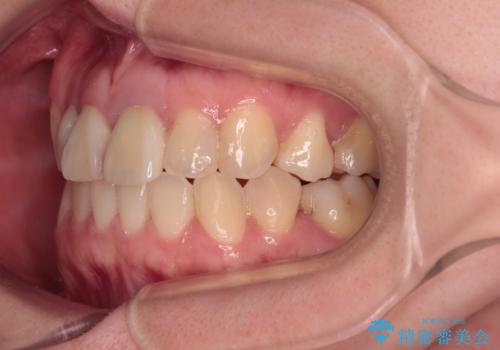

- 奥歯が痛いとのことで来院された患者様です。

上顎親知らず周辺の炎症と、神経組織の失活した歯の炎症による痛みが認められたため、親知らずの抜歯と根管治療を行いました。

根管治療を行った歯はクラウンによる補綴治療が必要となりますが、高校生の頃に行った矯正治療の後戻りも気になるとのことで、補綴治療を行う前に矯正治療を行うこととしました。

後戻りは軽度であり、インビザラインにて歯列を整え、その後にオールセラミッククラウンにて補綴治療を行うこととしました。